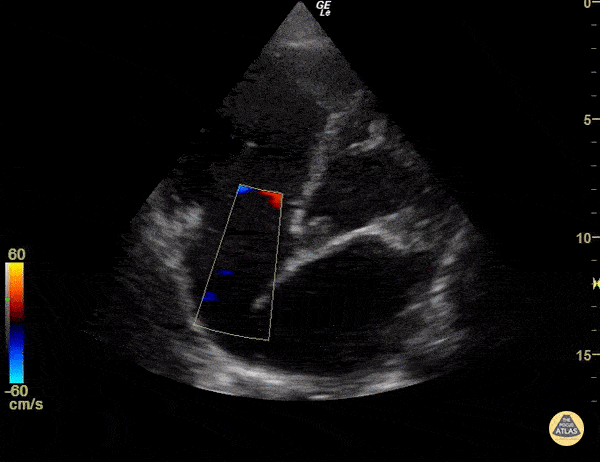

Significant right ventricular dysfunction with moderate tricuspid regurgitation Sukh Singh, MD